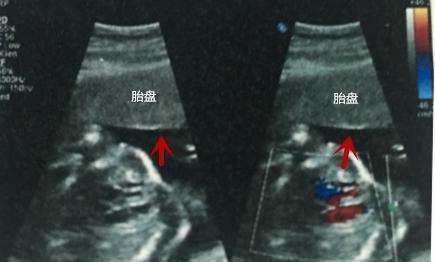

S/D:代表所监测血流的阻力指数之一

S/D值的变化是掌握胎儿发育是否正常的重要指标。

胎儿脐动脉收缩压与舒张压的比值与胎儿供血相关,当胎盘功能不良或脐带异常时此比值会出现异常,在正常妊娠情况下,随孕周增加胎儿需要增加S下降,D升高,使比值下降,近足月妊娠时S/D小于3。

Cord:脐带

正常情况下,脐带应漂浮在羊水中,如在胎儿颈部见到脐带影像,可能为脐带绕颈。

在黑白灰阶超声检查报告单上,有时可以看见写有胎儿“颈部有压迹”,这就是指脐带绕颈。

根据脐带缠绕颈部的圈数可见U形、W形和品字形。有的B超检查单还会直接注明“脐带绕颈一周”的字样。